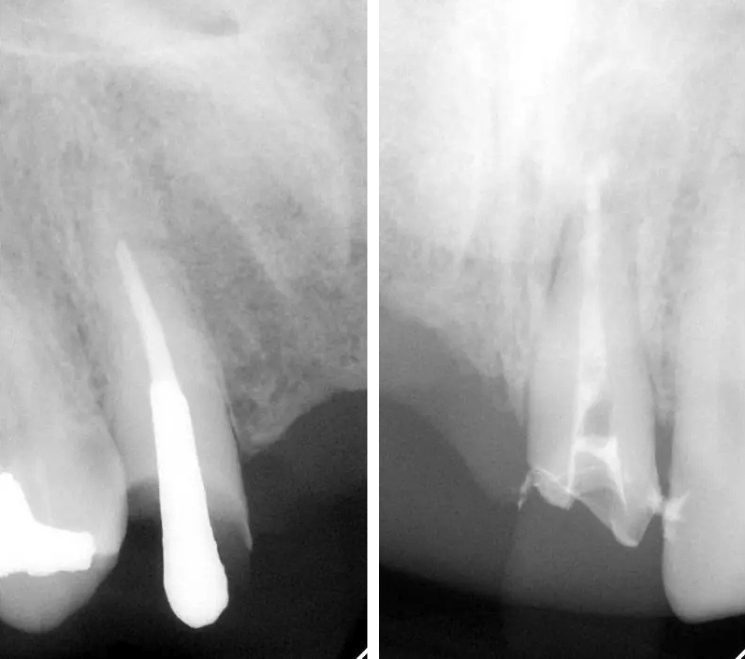

インプラント治療の症例紹介⑨

Before

After

主訴

前歯が揺れる、咬むと痛い

治療内容

抜歯後骨造成手術を行い、その後インプラント埋入手術を行いました。

治療費

462,000円(税込)

治療期間

7ヶ月

通院回数

15回

想定されたリスク

※経年的な歯肉退縮の恐れ.インプラント周囲炎の恐れがありました。

濱 仁隆先生

浜歯科

外傷により歯根破折を生じたケース。骨欠損が大きかったので骨造成術を行い、審美ゾーンにインプラント補綴を行った症例です。